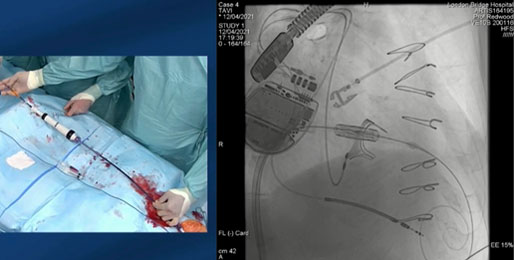

La réparation percutanée de la valve mitrale

La réparation percutanée dite "bord à bord" de la valve mitrale a été largement présentée, avec une discussion des indications des principaux résultats cliniques. Pour chaque système, les étapes clefs ont été détaillées de façon très didactique avec des astuces pratiques pour faciliter les procédures. La session du 20 mai en Main Arena (15h35 -17h00) pour le MitraClip (Abbott Vascular) ou la session du 18 mai sur la chaîne valvulaire (14h00 à 15h30) pour le système PASCAL (Edwards Lifesciences).

Il faut savoir que d’autres techniques existent, comme l’annuloplastie percutanée avec les systèmes d’annuloplasties indirectes (Carillon Mitral Contour System ou l’ARTO system) ou les systèmes d’annuloplasties directes (Cardioband Mitral System ou Millipede system). De plus, la réparation de cordage percutanée est possible avec le NeoChord ou le HARPOON system.

Le remplacement percutané de la valve mitrale

Durant les 10 dernières années, plusieurs solutions de réparation valvulaire percutanée ont été développées pour traiter les IM sévères, avec une importante efficacité et sécurité. Cependant, certaines situations anatomiques ne permettent pas de proposer une réparation percutanée optimale, comme la présence de calcification valvulaire mitrale ou encore un mécanisme de restriction valvulaire majeur.

Actuellement, les données de la littérature sur le remplacement percutané de la valve mitrale restent limitées. Cependant, les premières données des premiers patients porteurs d’une IM majoritairement d’origine secondaire, ayant bénéficié de l’implantation percutanée d’une valve mitrale avec l’une des 7 technologies disponibles sont encourageantes avec une mortalité opératoire de 2%, une mortalité à 30 jours de 13%, un taux de succès de la procédure de 92% et un phénomène obstructif de la chambre de chasse a été retrouvé dans 4 % des cas (30954209). Le système ayant le plus d’expérience clinique à ce jour est le Tendyne (Abbott Vascular) qui a été présenté lors de la session du 18 mai de 12h à 13h.

Lors d’une dégénérescence d’une bioprothèse mitrale chirurgicale, le traitement devient le traitement par valve-in-valve (session du 18 mai, chaîne valvulaire de 15h30 à 17h).